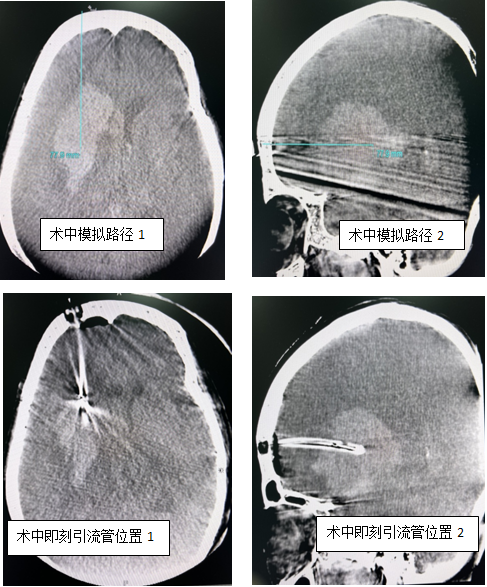

先进的复合手术室,使用局部浸润麻醉、术中CT引导、经眶上(血肿纵轴)行颅内血肿钻孔引流术。手术当日,患者仰卧位行DynaCT评估并模拟穿刺路径、方向及深度,标记右侧眶上约3cm长切口,切开皮肤后颅骨钻小孔并切开硬膜,按预先模拟路径将引流管穿刺至血肿中心部位,再次行DynaCT明确引流管位置,缓慢抽吸出约25ml暗红色血肿,留置引流管于血肿腔并固定,术后持续引流5天后复查示大部分血肿消失,给予拔出引流管,患者恢复顺利,已转至普通病房继续对症治疗。